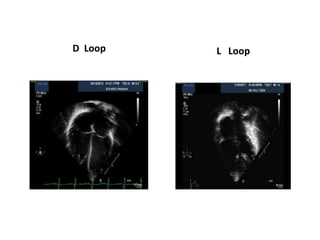

Ventricular Looping

• Embryonic heart is a linear tube with bulbus cordis (future RV )

being cephalad to the developing left ventricle (LV) .

• In normal development the tube bends over on itself to right

forming a D-loop resulting in positioning of the bulbus cordis to the

anatomic right of the left ventricle

• Folding to left results in L-loop with the morphologic right ventricle

being to the left of the morphologic left ventricle

D Loop L Loop